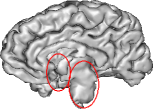

To further investigate the smoothing effect of our reconstruction algorithm, gray matter interface of the cortical surface has bee extracted using the above mentioned BrainVISA pipeline. Extracted surfaces (medial and lateral views) from mSENSE and 3D-UWR-SENSE images are show in Fig. 3 for . For comparison purpose, we provide results with mSENSE at as ground truth.

For the lateral view, one can easily conclude that extracted surfaces are very similar.

However, the medial view shows that mSENSE is not able to correctly segment the brainstem (see right red ellipsoid in

the mSENSE medial view). Moreover, results with mSENSE are more noisy compared to 3D-UWR-SENSE (see left red ellipsoid

in the mSENSE medial view). In contrast, the calcarine sulcus is slightly less accurately extracted with

our approach.

It is also worth noticing that similar results have been obtained on 14 other subjects.